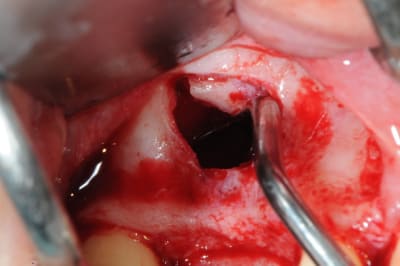

les premières photos, c'était ouverture par voie latérale

les suivantes;

- forage et transperçage de la crête sans aller trop loin...

- essayage pilier pour parallélisme

- forage à 3mm

- visualisation de la hauteur sous la membrane de Schneider

- utilisation d'un ostéotome diamètre 3.4 puis 3.8

(sous dimensionnement de diamètre par rapport à l'implant prévu :4mm)